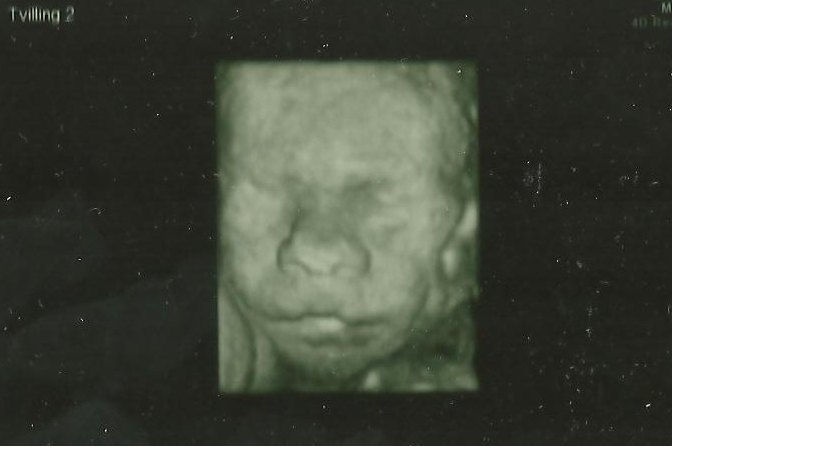

13+1 tvillinge b/Isabella